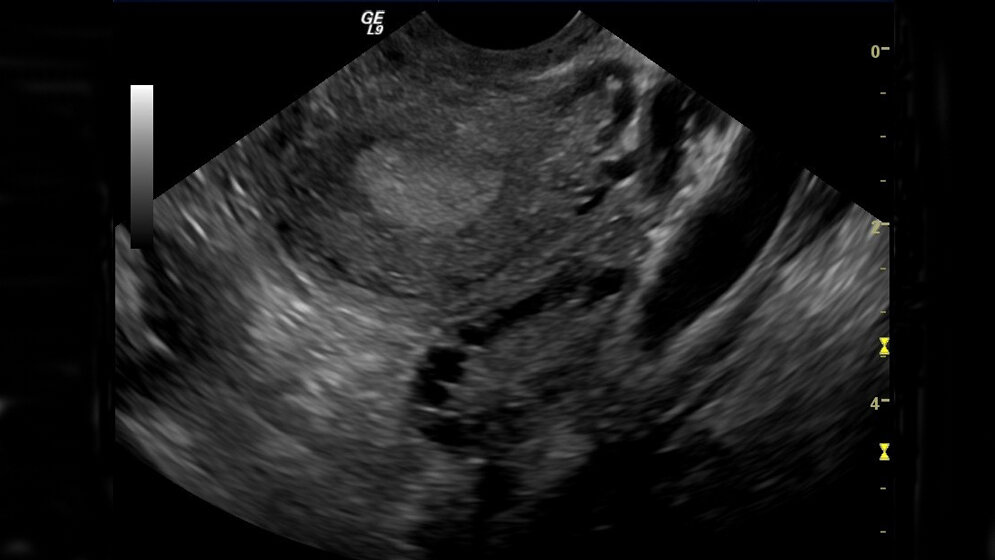

Etwa fünf bis acht Prozent der Frauen leiden an einem Polyzystischen Ovar-Syndrom (PCOS). Es hat zur Folge, dass der Eisprung nur selten stattfindet. Hier kann eine zweiwöchige Gestagen-Gabe in der zweiten Zyklushälfte die Wahrscheinlichkeit eines Eisprungs im nächsten Zyklus der Patientin mit einem milden PCOS erhöhen.